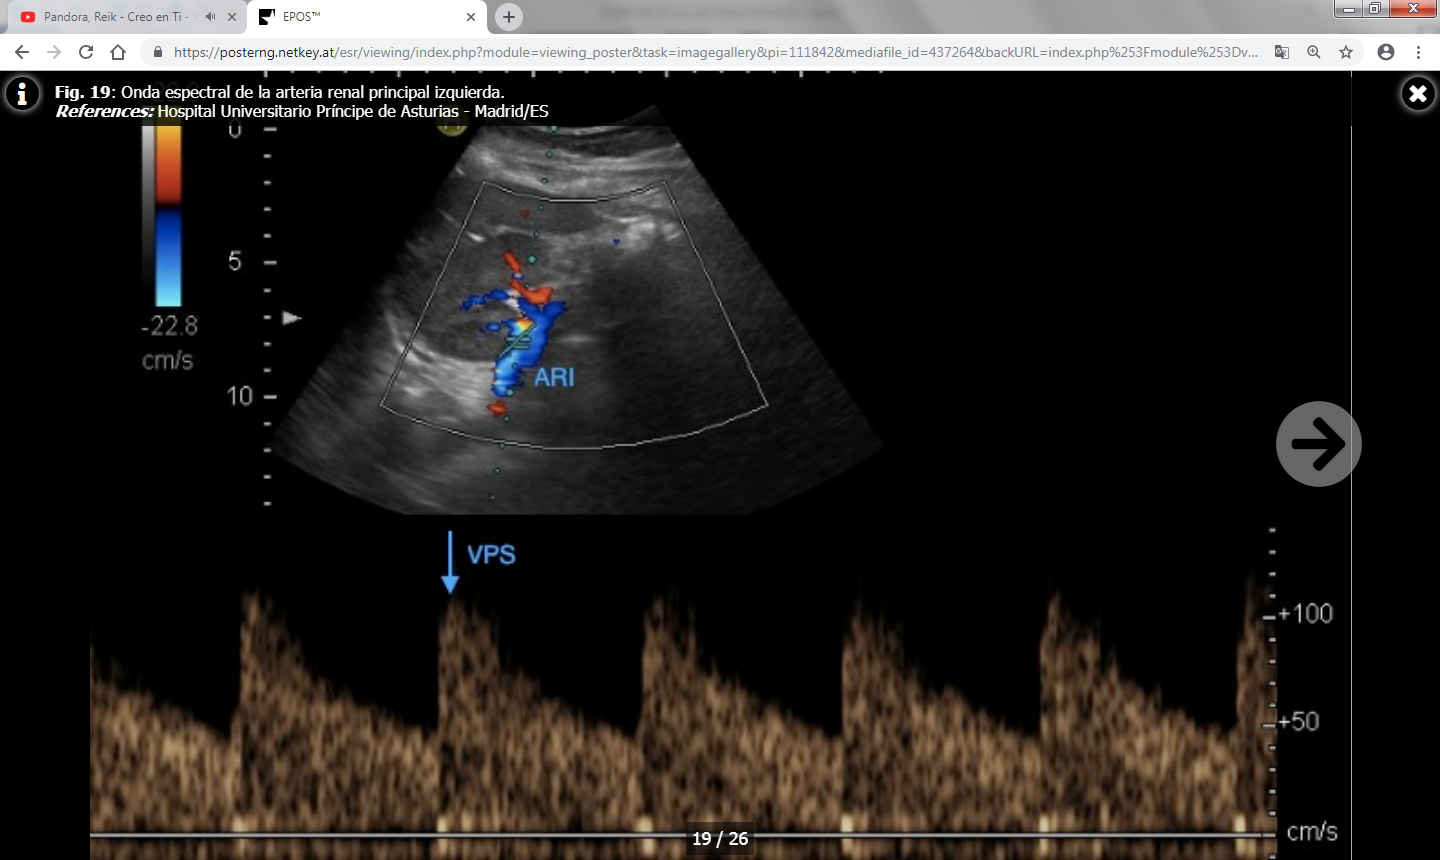

- Velocidad picosistólica (VPS) : Normal por debajo de 180-200 cm/s.

- Índice reno-aórtico (cociente entre la VPS de la arteria renal y la aorta): Normal por debajo de 3.5-3.6.

- Índice reno-renal (cociente entre la VPS en el punto de estenosis y en un punto distal a la misma): Normal por debajo de 4.